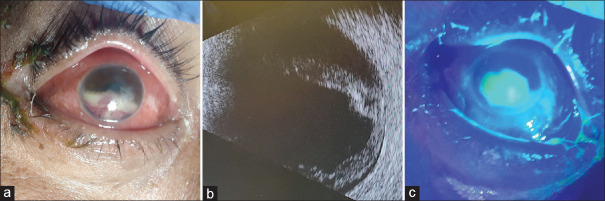

紫丁香紫霉(PL)是一种罕见的真菌角膜炎原因。PL角膜炎的治疗是复杂的诊断延迟,耐局部抗真菌治疗,并经常需要手术干预。我们报告一例PL角膜炎患者有显著的甲基苯丙胺使用史,最初表现为右眼持续角膜上皮缺损,并伴有大量眼内炎症,其证据为出血性垂体后叶。尽管使用多种抗菌药物(包括局部和全身伏立康唑)延长了疗程,但患者最终接受了穿透性角膜移植术治疗角膜穿孔。我们的病例是甲基苯丙胺使用者中首次记录的PL角膜炎,突出了他们对感染性角膜炎(包括真菌性角膜炎)的脆弱性增加。它也证明了PL角膜炎的挑战性和往往旷日持久的临床过程,这往往需要积极的医疗和手术干预。

Purpureocillium lilacinum (PL) is an infrequent cause of fungal keratitis. Treatment of PL keratitis is complicated by delayed diagnosis, resistance to topical antifungal treatments, and the frequent need for surgical intervention. We report a case of PL keratitis in a patient with a significant history of methamphetamine use who initially presented with a persistent corneal epithelial defect in the right eye and associated exuberant intraocular inflammation as evidenced by a hemorrhagic hypopyon. Despite an extended treatment course with multiple antimicrobial agents, including topical and systemic voriconazole, the patient ultimately underwent penetrating keratoplasty for corneal perforation. Our case represents the first documented instance of PL keratitis in a methamphetamine user, highlighting their increased vulnerability to infectious, including fungal, keratitis. It also demonstrates the challenging and often protracted clinical course of PL keratitis, which often requires both aggressive medical and surgical interventions.